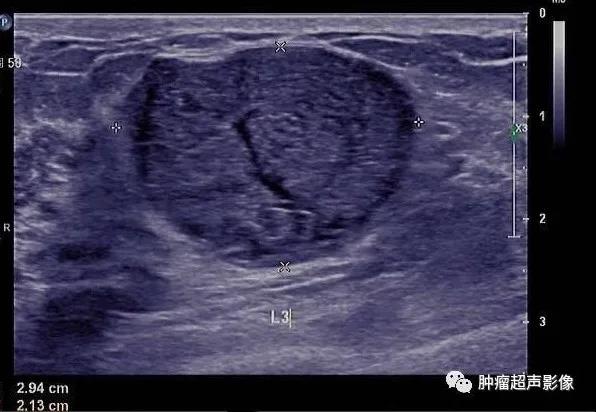

良性叶状肿瘤:女,39,肿块大小4.7㎝,边界清,假包膜,典型裂隙状,血流丰富,表现为典型叶状肿瘤超声表现,但是与交界性难以区分。